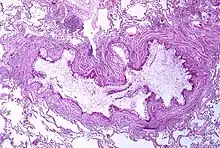

Pathophysiology

Asthma is the result of chronic inflammation of the conducting zone of the airways (most especially the bronchi and bronchioles), which subsequently results in increased contractability of the surrounding smooth muscles. This among other factors leads to bouts of narrowing of the airway and the classic symptoms of wheezing. The narrowing is typically reversible with or without treatment. Occasionally the airways themselves change.[22] Typical changes in the airways include an increase in eosinophils and thickening of the lamina reticularis. Chronically the airways' smooth muscle may increase in size along with an increase in the numbers of mucous glands. Other cell types involved include T lymphocytes, macrophages, and neutrophils. There may also be involvement of other components of the immune system, including cytokines, chemokines, histamine, and leukotrienes among others.[21]